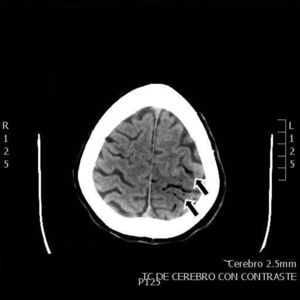

Our patient was a 55-year-old woman, a smoker (15 cigarettes/day) who presented chronic obstructive pulmonary disease, depressive disorder, and systemic lupus erythematosus (with lupus nephritis and antiphospholipid syndrome). The patient was receiving escitalopram, salbutamol, and acenocoumarol. She was admitted due to abdominal pain of 10hours’ progression, due to a duodenal perforation. She underwent emergency surgery, with suture and Graham patch of the anterior wall of the duodenal bulb by midline laparotomy. During the intervention, a CVC had to be placed in the right internal jugular vein (guided by ultrasound) to be used for parenteral nutrition in the immediate postoperative period. The procedure was uneventful and the patient was transferred to the recovery room, where she stayed for 12hours with no complications and started parenteral nutrition. She was subsequently transferred to an admission ward. At 48hours, immediately after replacement of the parenteral nutrition bag with the patient in a seated position, she presented an abrupt decrease in the level of consciousness, with quadriparesis, gaze deviation to the left, and facial droop. Arterial blood pressure, heart rate, and oxygen saturation values were normal. An emergency cranial CT scan (Fig. 1) revealed pneumocephalus with intraparenchymal air bubbles in the border zone of the middle cerebral artery and left anterior cerebral artery, and in arachnoid sulci of the left parietal convexity, compatible with air embolism. When her level of consciousness recovered, the patient presented right-sided hemiplegia and dysarthria, and was transferred to be treated with hyperbaric oxygen. An MRI study performed at 48hours (Fig. 2) revealed an extensive area of vasogenic cerebral oedema compatible with acute/subacute ischaemic lesions. An echocardiogram showed no evidence of heart disease, valvulopathy, or intracardiac shunts. Despite 4 sessions of treatment in a hyperbaric chamber with administration of 100% oxygen at 2.2 atmospheres for 60minutes, the patient showed no clinical improvement, with the right hemiplegia and dysarthria persisting. When she was discharged, the patient presented paresis of the right upper and lower limbs (3/5 in both) and hypoaesthesia, with altered positional sensitivity and inability to hold a standing position or walk, making her dependent in the activities of daily living. The Barthel Index score was 15/100.